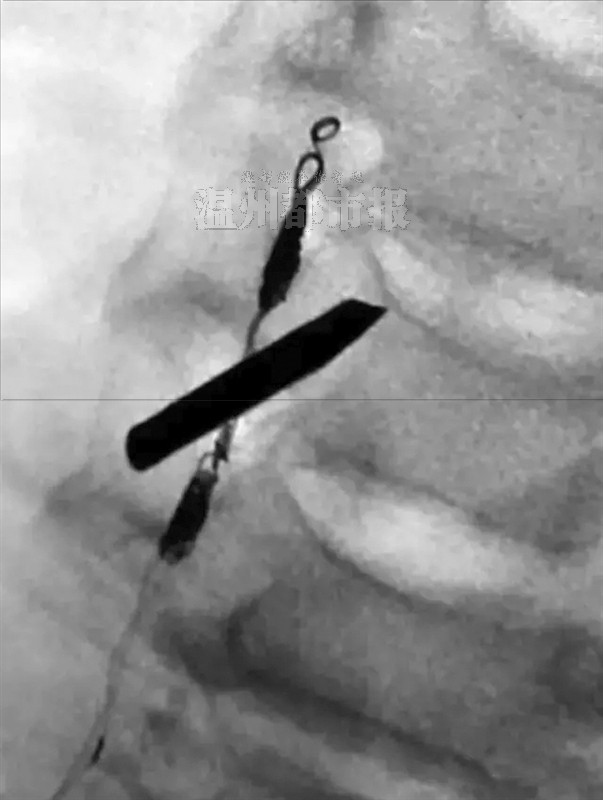

▲患者所拍的片子。下图与“铁钉”交叉物体为医生植入的栓塞。

神经外科的尹波医师第一个登台,在介入手术室内为患者施行“右椎动脉远近端栓塞术”。医生先是在郑其仁的右侧股动脉打个小洞,然后将一根带有球囊的细丝从股动脉伸入,慢慢地往出血位置推进,在X光线下寻找出血点。找到后,医生就会释放细丝中的球囊,将出血点堵住,以求止血。

尹波说,找到出血点是手术的第一关,第二关是寻找最适合的止血位置。“距离出血点太远,容易堵塞其他未损伤的血管,影响病人的血液供应;距离出血点太近,又不能很好地止血。”历时2个多小时,尹波终于将球囊释放,成功止住了右侧椎动脉的出血。尽管身处空调房,但他穿在防护服下的衣服早已湿透。